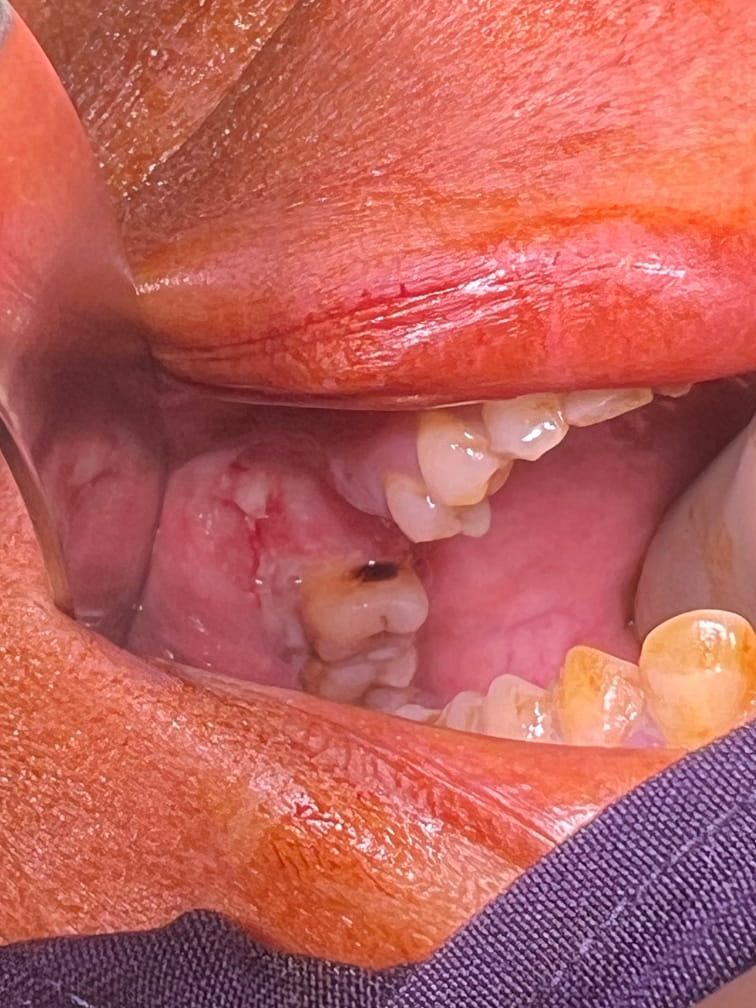

42 years old male suffering from right lower Gingivo buccal growth involving mandible .CT scan shows level 1 ,2 lymphadenopathy .Right modified neck dissection with right hemimandibulectomy with right pectoralis flape done.

21-04-2026